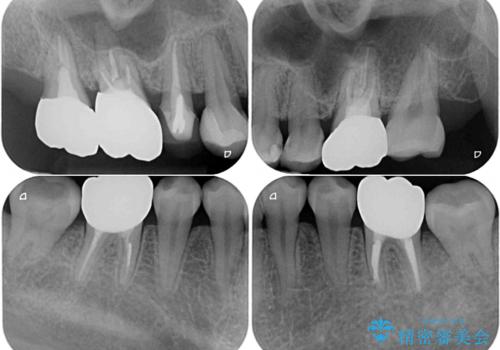

- 捻れた前歯と目立つ銀歯を気にして来院された患者様です。

左下大臼歯は根管治療が必要であったため、矯正治療前に根管治療を行い、その後矯正治療を行うこととしました。

矯正治療後には期にある銀歯を全てセラミッククラウンなどで補綴治療することとしました。

インビザライン・ライトによる矯正治療であったので、時間をかけずに治療を終えることができました。

口を開ける度に目立っていた銀歯もセラミックで自然な口元の印象となりました。